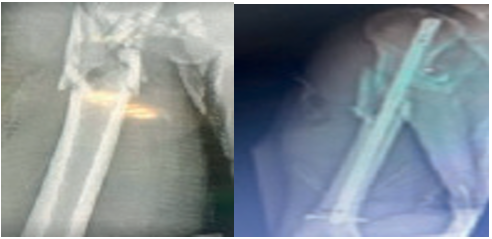

Figure 3

Figure 3. (1)Femur Fracture - Preoperative Radiograph (2) Postoperative Radiograph of Femoral Intramedullary Nailing (3) Type 3C Femur Fracture with Vascular Injury